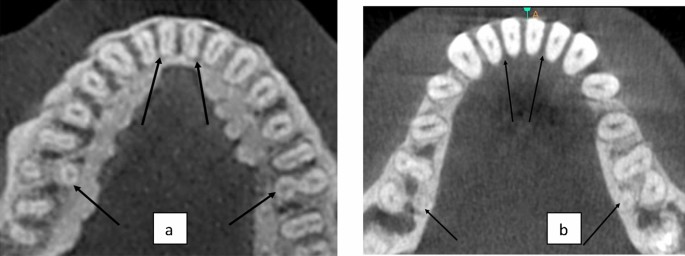

Prevalence of DLRs

A total of 400 scans exhibiting 800 MFMs were assessed for the presence of DLR. Of the 800 MFMs evaluated, 6.62% (53 of 800) exhibited DLR. Of the total 800 MFMs evaluated, 7.8% (31 out of 400) right and 5.5% (22 out of 400) left MFMs exhibited distolingual roots (p > 0.01)(Table 2) (Fig. 4). Of the total 400 scans examined, 3.5% (14 out of 400) showed the unilateral presence of DLRs. However, the prevalence of bilateral DLRs in the MFMs was found to be 5% (20 out of 400) (Fig. 5).According to the gender-wise distribution of DLR, 9.5% (38 out of 400) males and 3.75% (15 out of 400) females showed presence of DLR (p > 0.05 on right and left) (Table 3). Age-wise distribution of DLR in MFM showed more prevalence in the age group above 44 years on both the right and left side that is 8.5% (34 out of 400) and 4.75% (19 out of 400) in groups less than 44 years (p > 0.05 on right and left) (Table 4). There was no statistically significant difference in the distribution of DLR in MFM among age, sex, and side (p > 0.05).

Overall, the prevalence of complicated root canal configuration of the mandibular right and left central incisors in the presence of the first molar with DLR was 32% (128 of 400) and 34.5% (138 of 400) respectively. Approximately 7.8% (31 of 400) and 5.5% (22 of 400) of the permanent MFMs exhibited DLRs on the right and left sides, respectively. In the presence of DLRs, 27.2% (9 of 33) and 30.3% (10 of 33) of the central incisors showed complicated root canal configurations on the right and left sides, respectively. In the absence of DLRs, 32.4% (119 of 367) and 34.8% (128 of 367) of the central incisors showed complicated root canal morphology on the right and left sides, respectively. Therefore, the frequency of complicated root canal morphology in MCIs was more in the absence of DLR in MFMs as compared to the presence of DLR (p > 0.05 on right and left) (Table 8).

Since the p value is more than 0.05, null hypothesis is accepted that there is no correlation between presence of DLR and complicated root canal anatomy in MCIs (Fig. 7).

In relation to the lateral incisors

Overall, In the presence of the first molar with DLR, the prevalence of a complicated root canal configuration of the mandibular right and left lateral incisors was 41.75% (167 of 400) and 41% (164 of 400), respectively. Approximately 7.8% (31 of 400) and 5.5% (22 of 400) of the permanent MFMs exhibited DLRs on the right and left sides, respectively. In the presence of DLRs, 39.3% (13 of 33) and 39.4% (13 of 33) of the lateral incisors showed complicated root canal configurations on the right and left sides, respectively. In the absence of DLRs, 41.9% (154 of 367) and 41.1% (151 of 367) of the lateral incisors showed complicated root canal morphology on the right and left sides, respectively. Therefore, the frequency of complicated root canal morphology in MLIs was more in absence of DLR in MFMs as compared to the presence of DLR (p > 0.05 on right and left) (Table 8).

Since the p value is more than 0.05, the null hypothesis is accepted that there is no correlation between the presence of DLR and complicated root canal anatomy in MLIs.